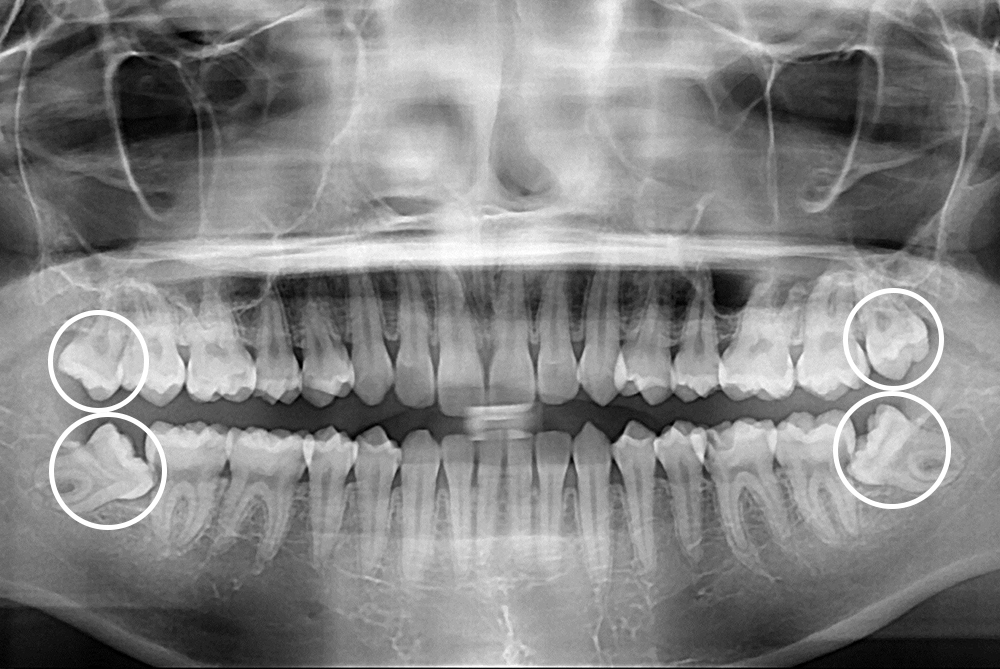

[사랑니] 매복 사랑니 발치

치료전 : 2018-09-12